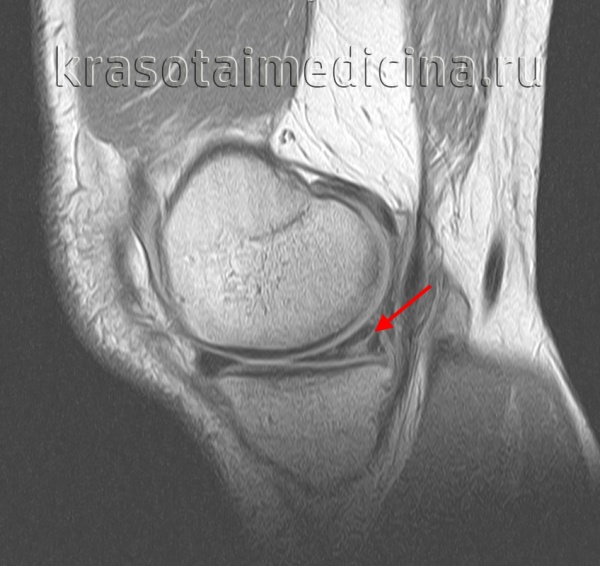

Для более точного определения тяжести повреждений применяется классификация по Stoller, основанная на объективных критериях, выявляемых при помощи магнитно-резонансной томографии. Согласно данной классификации выделяется 4 степени повреждения – от 0 (изменений нет) до 3 степени (полный разрыв).

МРТ применяется для определения малейших изменений в хрящевой ткани, а также классификации степени тяжести по Stoller. Артроскопия представляет собой инвазивный метод исследования с непосредственным осмотром структур колена при помощи артроскопа (оптический прибор в виде тонкой трубки, который оснащен видеокамерой, он вводится в полость сустава).

- МРТ. В настоящее время золотым стандартом диагностики считается МРТ коленного сустава, которая дает возможность детально изучить мягкотканные структуры сустава.